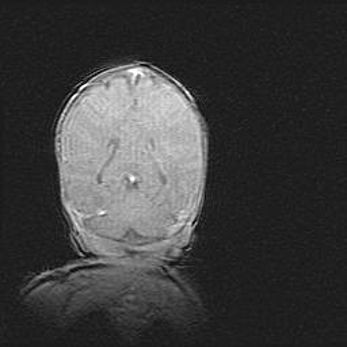

Церебральная ишемия II.

Возраст: 5 дней

Вес: 3400 г

Пол: женский

Окружность головы: 35 см

Срок гестации: 39 недель

Церебральная ишемия – это заболевание, характеризующееся недостаточностью (гипоксией) либо полным прекращением (аноксией) снабжения мозга кислородом по причине закупорки одного или нескольких сосудов. Это приводит к  что метаболическим расстройствам различной степени тяжести в тканях головного мозга, развитию коагуляционных некрозов и гибели нейронов.